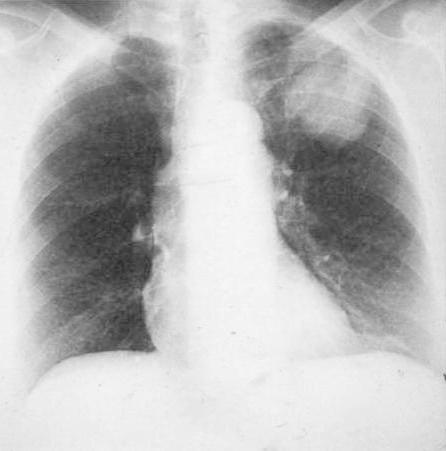

POSITION

of the SCAPULAE

They should project outside the lung fields

wrong--->

correct: